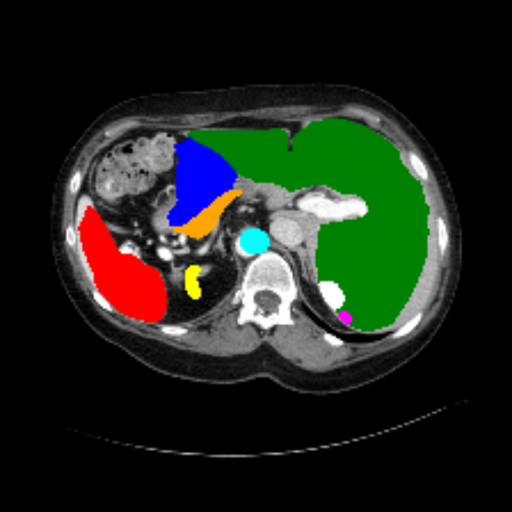

Figure 3 presents a qualitative comparison of segmentation performance on examples from the Synapse, BTCV, ACDC, and ISIC17 datasets. The first two examples (from Synapse) highlight variations in segmentation performance among U-Net, TransUnet, Mamba-Unet, and Swin-Unet. While Swin-Unet performs well in the first example, its performance decreases in the second example, particularly in segmenting the organ highlighted in blue. Additionally, it misclassifies background regions as the class highlighted in orange. In contrast, our approach demonstrates high robustness in segmenting all classes accurately and aligning well with the ground truth masks.

Refer to caption Refer to caption Refer to caption Refer to caption Refer to caption Refer to caption Refer to caption

Slice GT Unet TransUnet Mamba-Unet Swin-UMamba MambaCAFU-V1

Figure 3: Visual comparison of segmentation examples from Synapse (first two examples), BTCV (3-4 examples), ACDC (5th example) and ISIC17 (last example). Columns: input slice, ground truth, Unet, TransUnet, Mamba-Unet, Swin-UMamba, and MambaCAFU-V1.